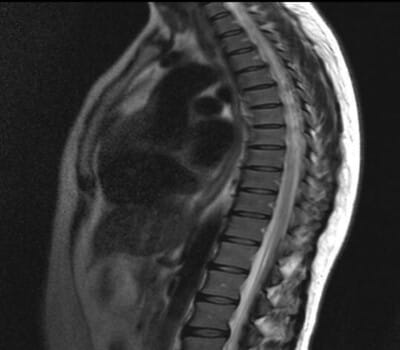

Компьютерная томография – метод, позволяющий уточнить состояние костной ткани и ее отдельных фрагментов. Применение мультиспирального компьютерного томографа позволяет сделать необходимое количество снимков за один проход и получить объемную проекцию для детального изучения структуры костной и соединительной ткани. МСКТ позвоночника позволяет установить наличие множественных патологий в позвонках и дисках, уточнить эффективность тактики лечения или выбрать оптимальную схему предстоящего хирургического вмешательства.

Исследование грудного или поясничного отдела позвоночника на МСКТ осуществляется по принципу рентгенографии. За один проход по спирали можно получить несколько десятков снимков в разных проекциях. Их объединение с помощью специального программного обеспечения позволяет увидеть позвоночник в 3D режиме и рассмотреть интересующую область со всех сторон для уточнения локализации патологического процесса. МСКТ позвоночника назначается пациентам при подозрении на остеохондроз, спондилез, повреждения позвонков и межпозвоночных дисков, а также – позволяет обнаружить кисты, гематомы, опухолевые процессы и т.д.

Что показывает снимок МСКТ

Благодаря снимку МСКТ удается обнаружить:

• изменения в костной ткани: снижение плотности, появление рыхлых участков, разрушения и т.д.;

• наличие опухолевых процессов или межпозвоночной грыжи;

• деформацию или патологические костные разрастания;

• нарушения структуры и смещение позвонков относительно центральной оси.

Используя принцип рентген-излучения, съемка на мультиспиральном томографе превосходит рентгенографию по качеству визуализации и информативности получаемых изображений. Если данных обследования недостаточно для точной постановки диагноза, пациент может быть направлен на магнитно-резонансную томографию. Оба исследования взаимно дополняют друг друга и предоставляют исчерпывающую картину состояния позвоночного столба и имеющихся патологий.